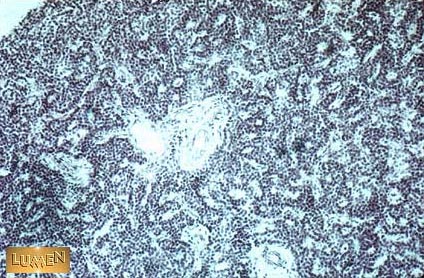

Identify this structure.

Answer

Parathyroid